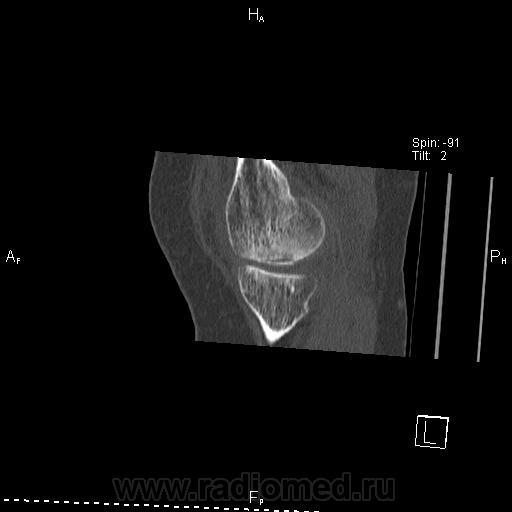

Здравствуйте! Давненько ничего не выкладывал. Нужна помощь. Женщина 1937 г.р. Жалобы на боли в правом коленном суставе уже давно. Долго ставили деф артроз.

Думаю что здесь частичный аваскулярный некроз медиального мыщелка бедренной кости. Ну а теперь вопросы:

3. Где выпот на КТ? Вижу в полости сустава и между мышцами по задней поверхности на уровне подколенной ямки( что это за сумка?). Забыл сделать реконструкцию с кернелем для мягких тканей, поэтому мягкие ткани такие пёстрые вышли, но выпот видно.

Да, но здесь часть эпифиза рассосалась, осталась только частично разрушенная субхондральная пластинка. Вот и думаю что это за стадия

А что скажете о некрозе? Какая стадия и как его описать. Как участок костной дестр. с частичным разрушением замыкательной пластинки? Ну тогда по описанию не очень будет похоже на асептический некроз.